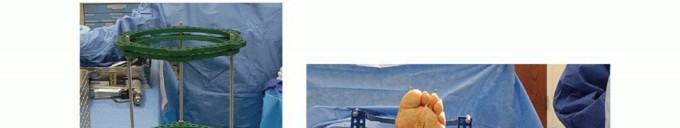

A three-level static neutral ring external fixation frame is assembled before surgery. The frame has limited adjustability to increase frame stability and minimize the risk for bolt or screw loosening. Note that the proximal ring can be “upsized” by one ring diameter size to accommodate the calf muscles (TECH FIG 1A).

The foot is centered within the closed foot ring with a two fingerbreadth clearance between the foot and the foot ring. Two olive wires are drilled through the calcaneus at a 30-degree angle to each other and parallel with the weightbearing surface of the heel. The wires are tensioned from 90 to 120 mm of tension and attached to the closed foot ring (TECH FIG 1B).

Two (three in large patients) olive wires are then drilled through the metatarsals at a 30-degree angle to each other and parallel with the weight-bearing surface of the foot. To avoid flattening the arch, each of these wires generally passes through only three metatarsals. The forefoot is compressed to the hindfoot by arch wire technique, where the wires are tensioned and then

attached to the foot ring one ring hole posterior to where they naturally lie (TECH FIG 1C).

Two olive wires are then drilled through the tibia at a 60-degree angle to each other, perpendicular to the weight-bearing axis of the tibia, at the level of the proximal ring. To avoid neurovascular injury, the wires are drilled through the bone and then carefully tapped through the soft tissues. With the tibia centered in the proximal ring, the wires are tensioned to 120 mm and attached to the proximal and middle rings.

Smooth wires are used in the center ring (TECH FIG 1D,E).

- TECH FIG 1 • A. A three-level static neutral ring external fixation frame is assembled before surgery. The

frame has limited adjustability to increase frame stability and minimize the risk for bolt or screw loosening.

Note that the proximal ring can be upsized by one ring diameter size to accommodate the calf muscles. B. The foot is centered within the closed foot ring with a two fingerbreadth clearance between the foot and the foot ring. Two olive wires are drilled through the calcaneus at a 30-degree angle to each other and parallel with the weight-bearing surface of the heel. The wires are tensioned from 90 to 120 mm of tension and attached to the closed foot ring. C. Two (three in large patients) olive wires are then drilled through the metatarsals at a 30-degree angle to each other and parallel with the weight-bearing surface of the foot. To avoid flattening the arch, each of these wires generally passes through only three metatarsals. The forefoot is compressed to the hindfoot by arch wire technique, where the wires are tensioned and then attached to the foot ring one ring hole posterior to where they naturally lie. D,E. Two olive wires are then drilled through the tibia at a 60-degree angle to each other, perpendicular to the weight-bearing axis of the tibia, at the level of the proximal ring. To avoid neurovascular injury, the wires are drilled through the bone and then carefully tapped through the soft tissues. With the tibia centered in the proximal ring, the wires are tensioned to 120 mm and attached to the proximal and middle rings. Smooth wires are used in the center ring.